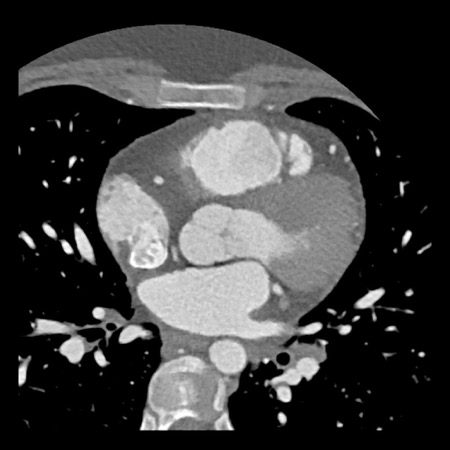

case 4 – CAD-RADS 3/P1/I+ thrombus left ventricle

First, scroll through the CTA images.

How would you describe the findings on the coronary CTA?

The findings are:

- Moderate (50-69%)

stenosis in the proximal LAD caused by a non-calcified plaque. - Variant of

sinoatrial (SA) nodal artery. The artery usually arises from the RCA as a second

branch after the conus artery, however in this case it arises from the LCX,

courses behind the aorta, anastomosing with the right atrium and with a small

branch supplies the SA-node of the heart. - Thrombus in the

apex of the left ventricle. - CTP was performed

in this patient. CTP showed a perfusion defect at stress imaging in the

territory of the LAD (I+), at rest no perfusion defect was visible.

This patient classifies as CAD-RADS 3/P1/I+, which means

this patient requires further investigation.